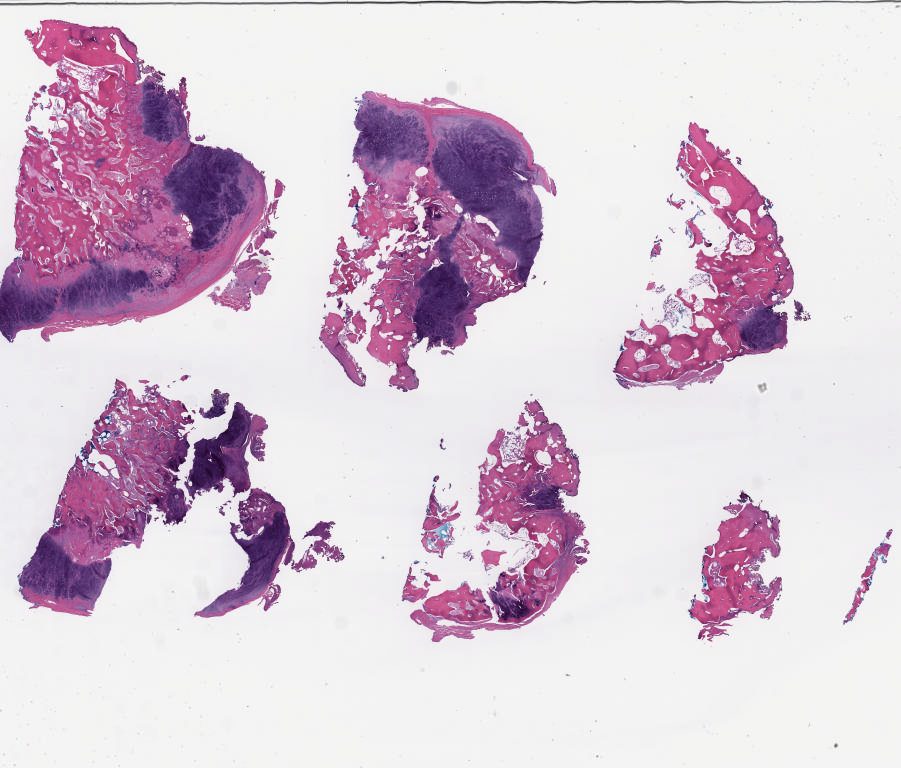

Case1.svs

105576

x

89958

@

40X